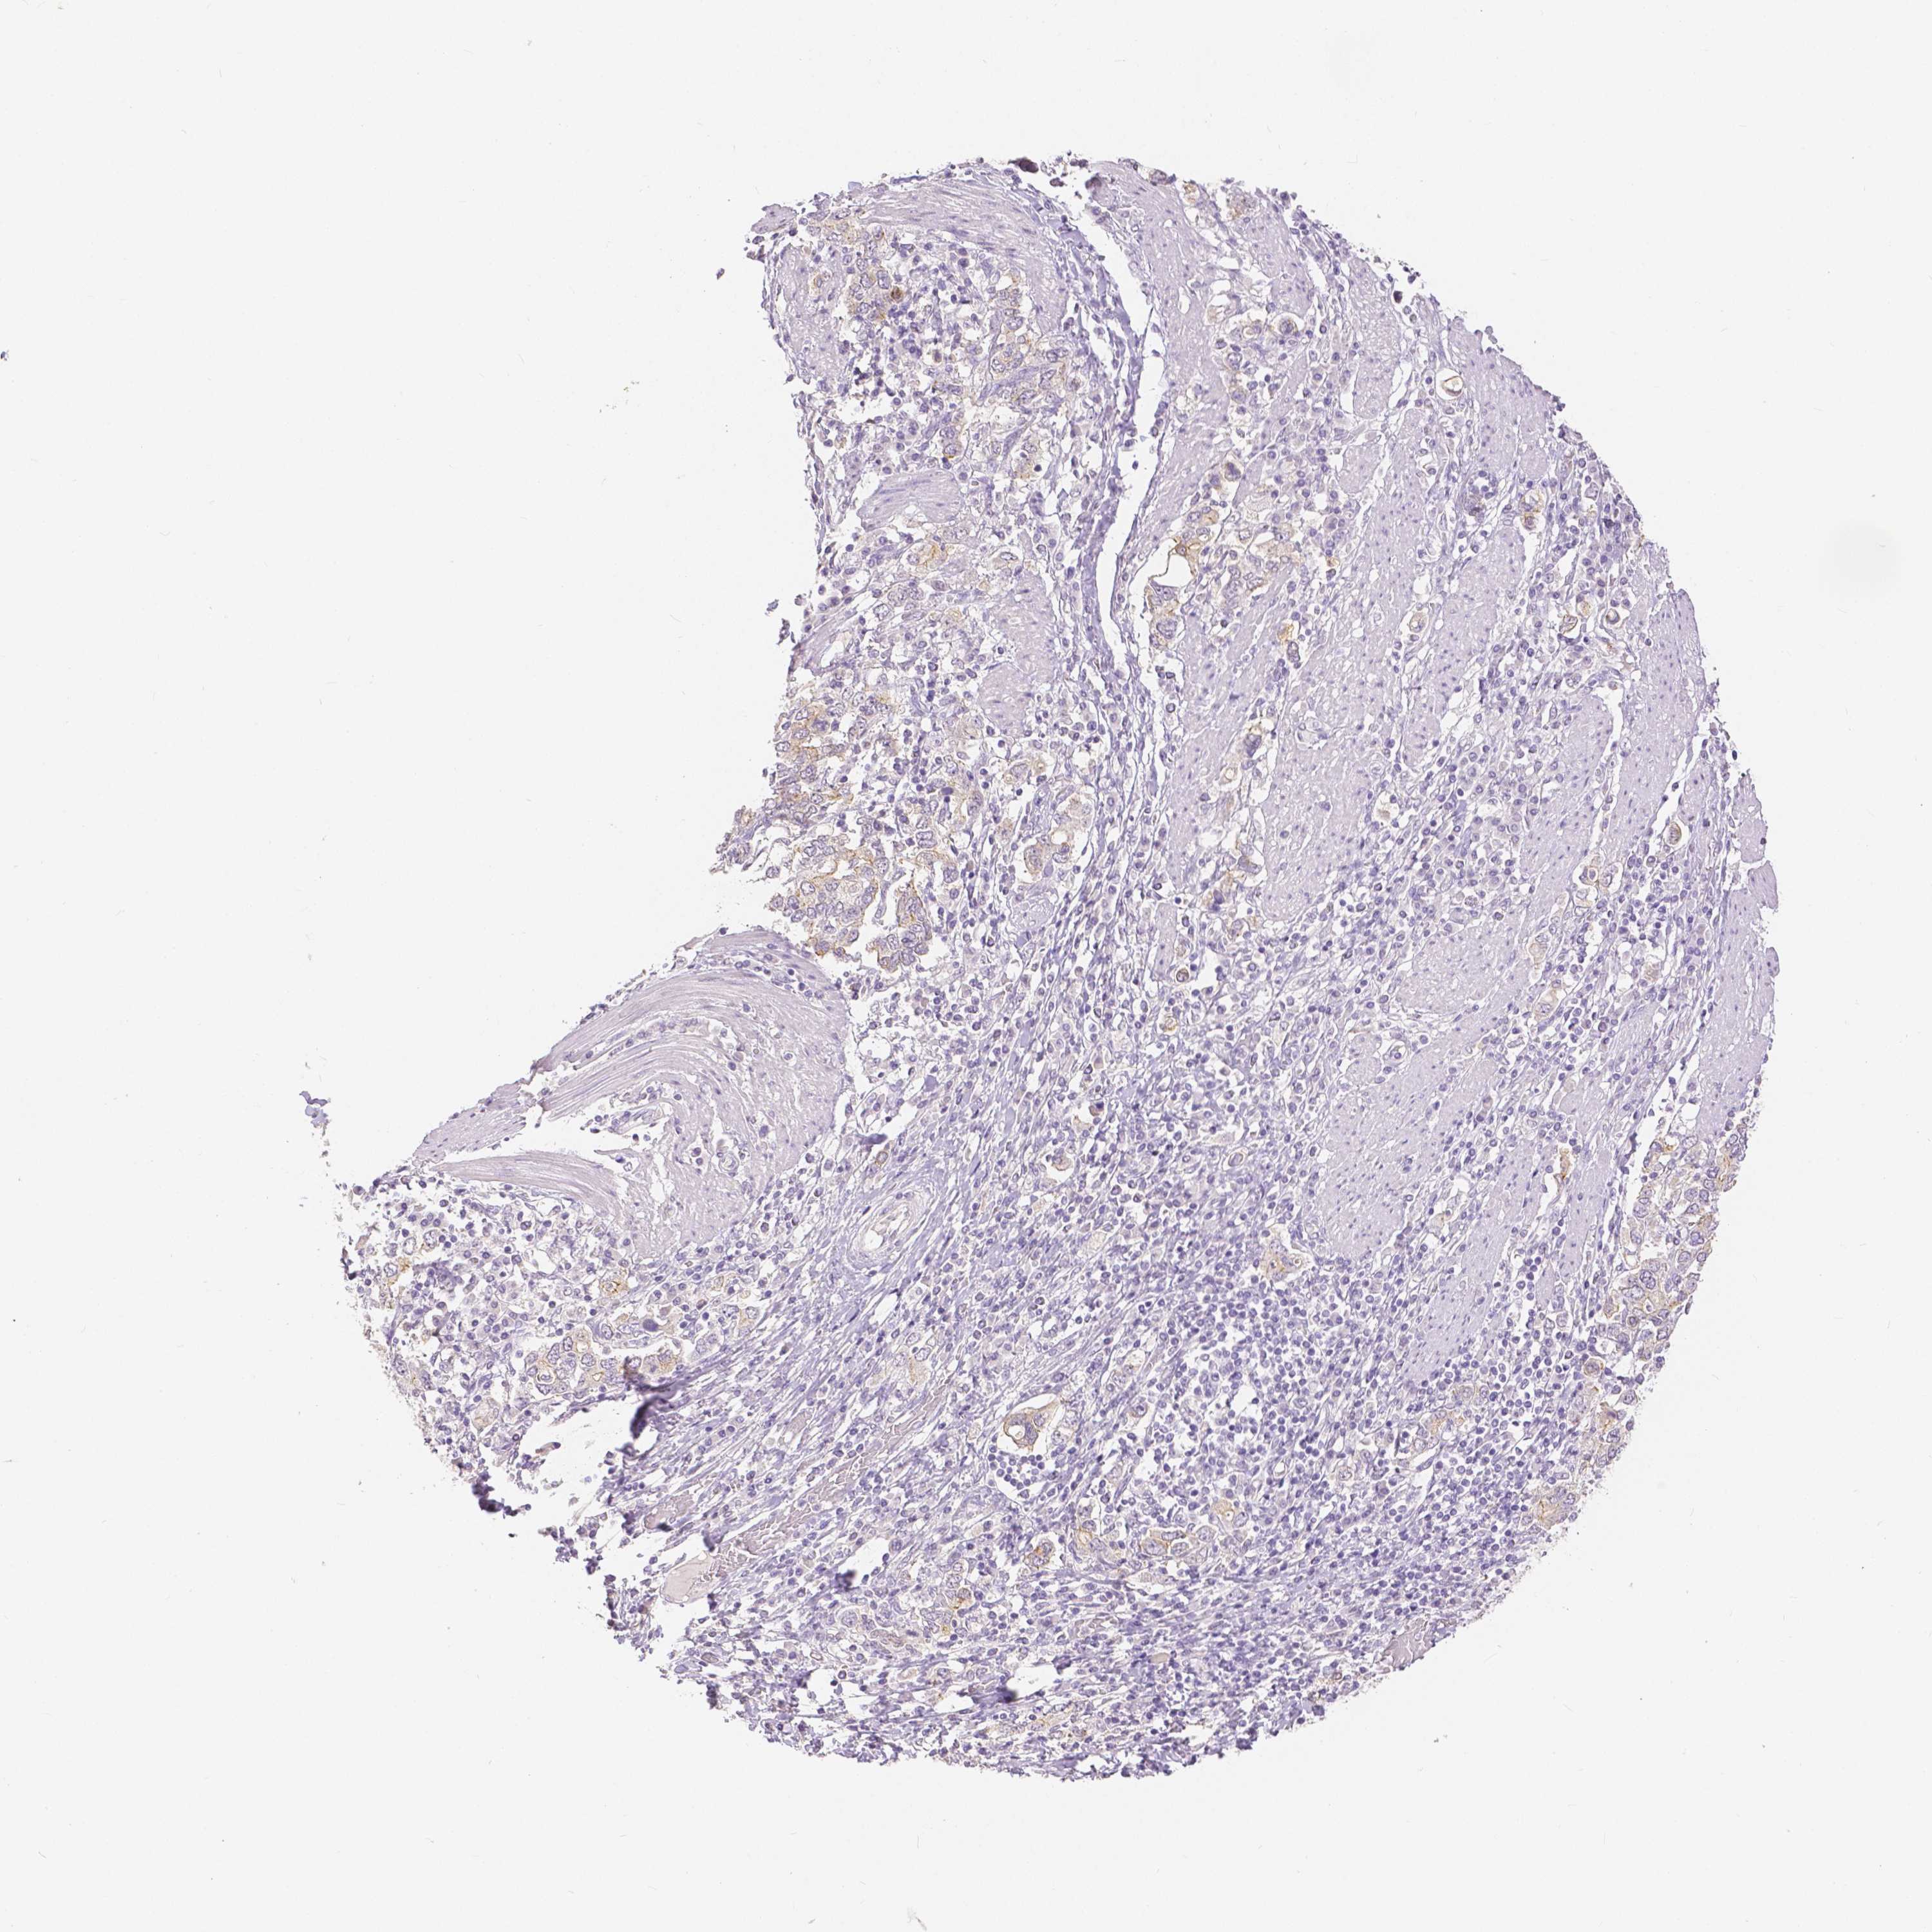

STOMACH CANCER - Protein expressioni

A mouse-over function shows sample information and annotation data. Click on an image to view it in a full screen mode. Samples can be filtered based on level of antibody staining by selecting one or several of the following categories: high, medium, low and not detected. The assay and annotation is described here.

Antibody stainingi

Antibody staining in the annotated cell types in the current human tissue is reported as not detected, low, medium, or high, based on conventional immunohistochemistry profiling in selected tissues. This score is based on the combination of the staining intensity and fraction of stained cells.

Each image is clickable and will lead to virtual microscopy that enables deeper exploration of all samples and also displays staining intensity scores, fraction scores and subcellular localization as well as patient and tissue information for each sample.

HPA005933

CAB013075

CAB068212

CAB068213

CAB068214

Staining

High

Medium

Low

Not detected

Intensity

Strong

Moderate

Weak

Negative

Quantity

>75%

75%-25%

<25%

None

Location

Nuclear

Cytoplasmic/membranous

Cytoplasmic/membranous,nuclear

Adenocarcinoma, NOS

Adenocarcinoma, High grade